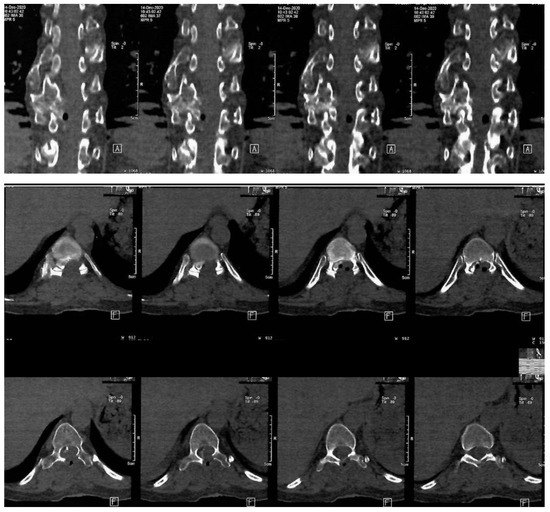

The patient underwent diagnostic evaluations with both MRI and CT scans (Figure 1), with the CT scan being particularly crucial for assessing bone and cartilage tissues, which are primarily affected in this disease. The imaging revealed an intracanalicular lesion at the T9–T10 level, compressing nerve roots and constricting the spinal cord. Additionally, she had osteochondromas at the right humerus, bilateral femurs, right tibia, and hip joints, along with numerous others along the spinal column. She also suffered from bilateral coxarthrosis and gonarthrosis, which severely limited her range of movement.

Figure 1. Preoperative CT scan. Note the intracanalar localization determined by the osteochondroma.

As shown in Figure 1, the osteochondroma occupied roughly three-quarters of the whole caliber of the medullary canal. Using the CT scan, the mass showed a bony signal with a homogenous composition. The shift of the spinal cord was very relevant, as the patient could not walk, or maintain orthostatism or sphincter control.